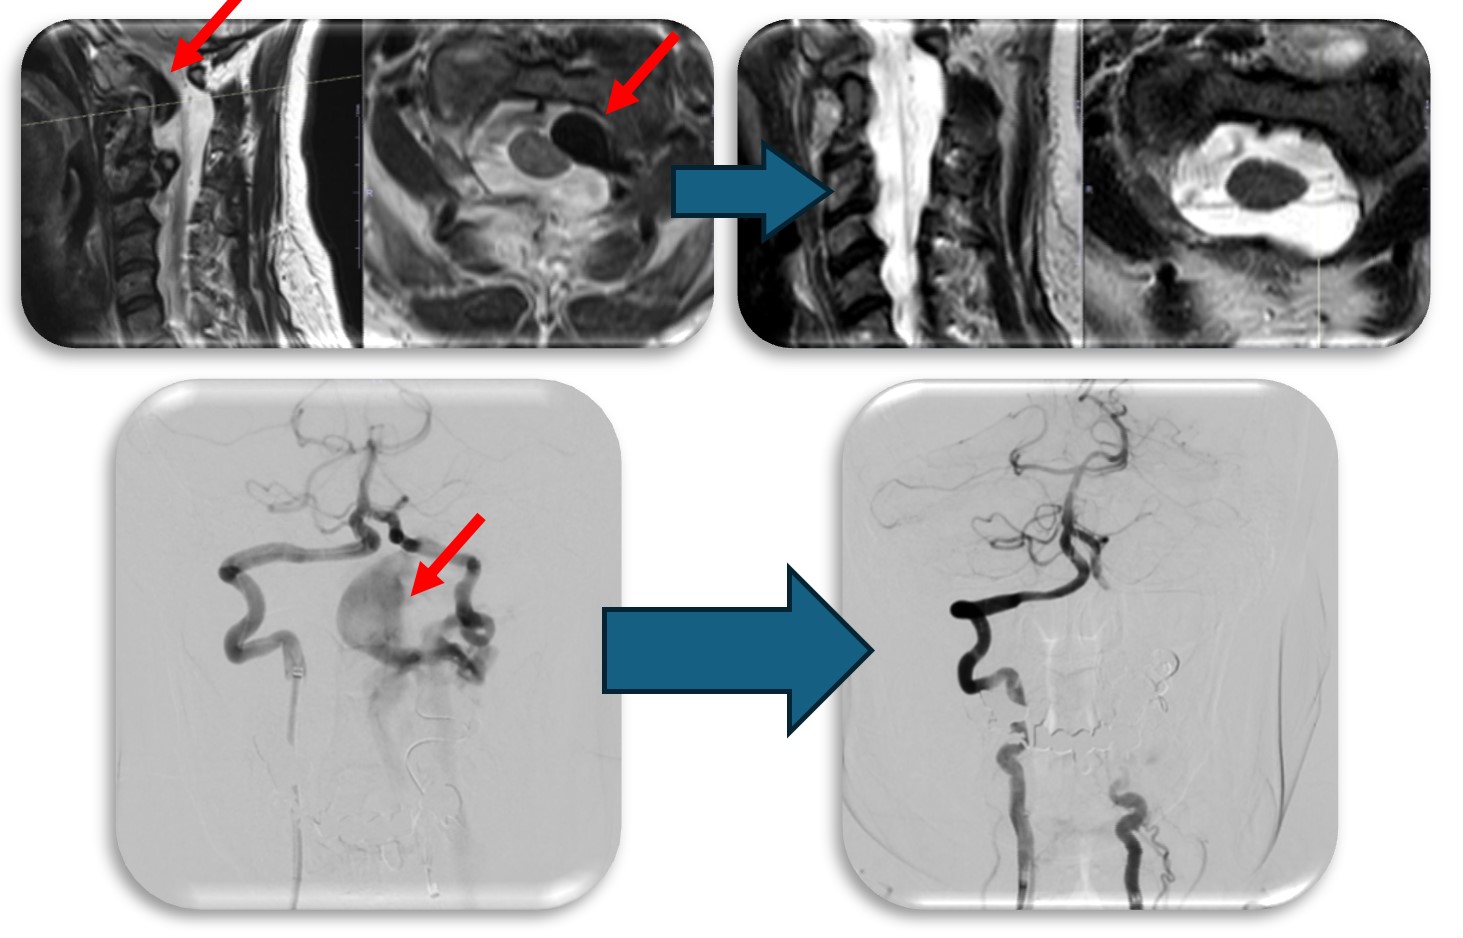

(代表例①)

硬膜動静脈瘻の症例です。脊髄血管奇形の中では最も多い疾患です。脊髄の静脈に動脈血流が直接流入する事により脊髄浮腫をきたし(赤矢印)、様々な神経症状が出ます。最近では血管内から治療することもありますが根治率は20%程度と非常に低く、基本的には高い確率で根治できる外科的治療を施します。当院では基本的には外科的治療を選択しますが、高齢者や外科的治療が困難な症例では血管内治療を検討することもあります。手術では動脈から静脈に直接流入する部位(緑矢印)を焼灼離断します。術直後に脊髄浮腫は改善し、造影CT検査で描出の認めた異常血管影(青矢印)は術後に消失しました。

(代表例②)

頚部にできた血管奇形の症例です。当初脊髄腫瘍という話で紹介された症例でしたが、巨大な血管奇形でした(赤矢印)。椎骨動脈と脊柱管内の静脈に異常なシャントが原因で巨大な静脈瘤を呈し、それが脊髄を圧迫し神経症状を来していました。この症例はもともと神経繊維腫症1型という遺伝子疾患の既往があったのですが、まれに頚椎や頚椎周囲の血管に奇形を呈することがあります。このような症例は外科的治療は危険性が非常に高く、血管内治療で治療しました。なお、この症例は環軸椎亜脱臼も呈しており今後時期を診て脊椎手術も行う予定です。